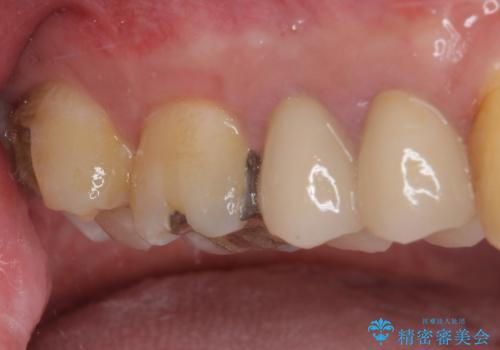

- 上の奥歯に装着されていた銀歯が外れてしまったとのことで来院された患者様です。

強い咬合力により銀歯と歯の間に隙間ができ、その隙間から虫歯となって外れてしまったと想像されました。

銀歯では歯と充填物の固さに違いがあり、再度外れてしまうリスクが高いため、固さが歯と近いゴールドインレー(PGAインレー)にて修復することとしました。